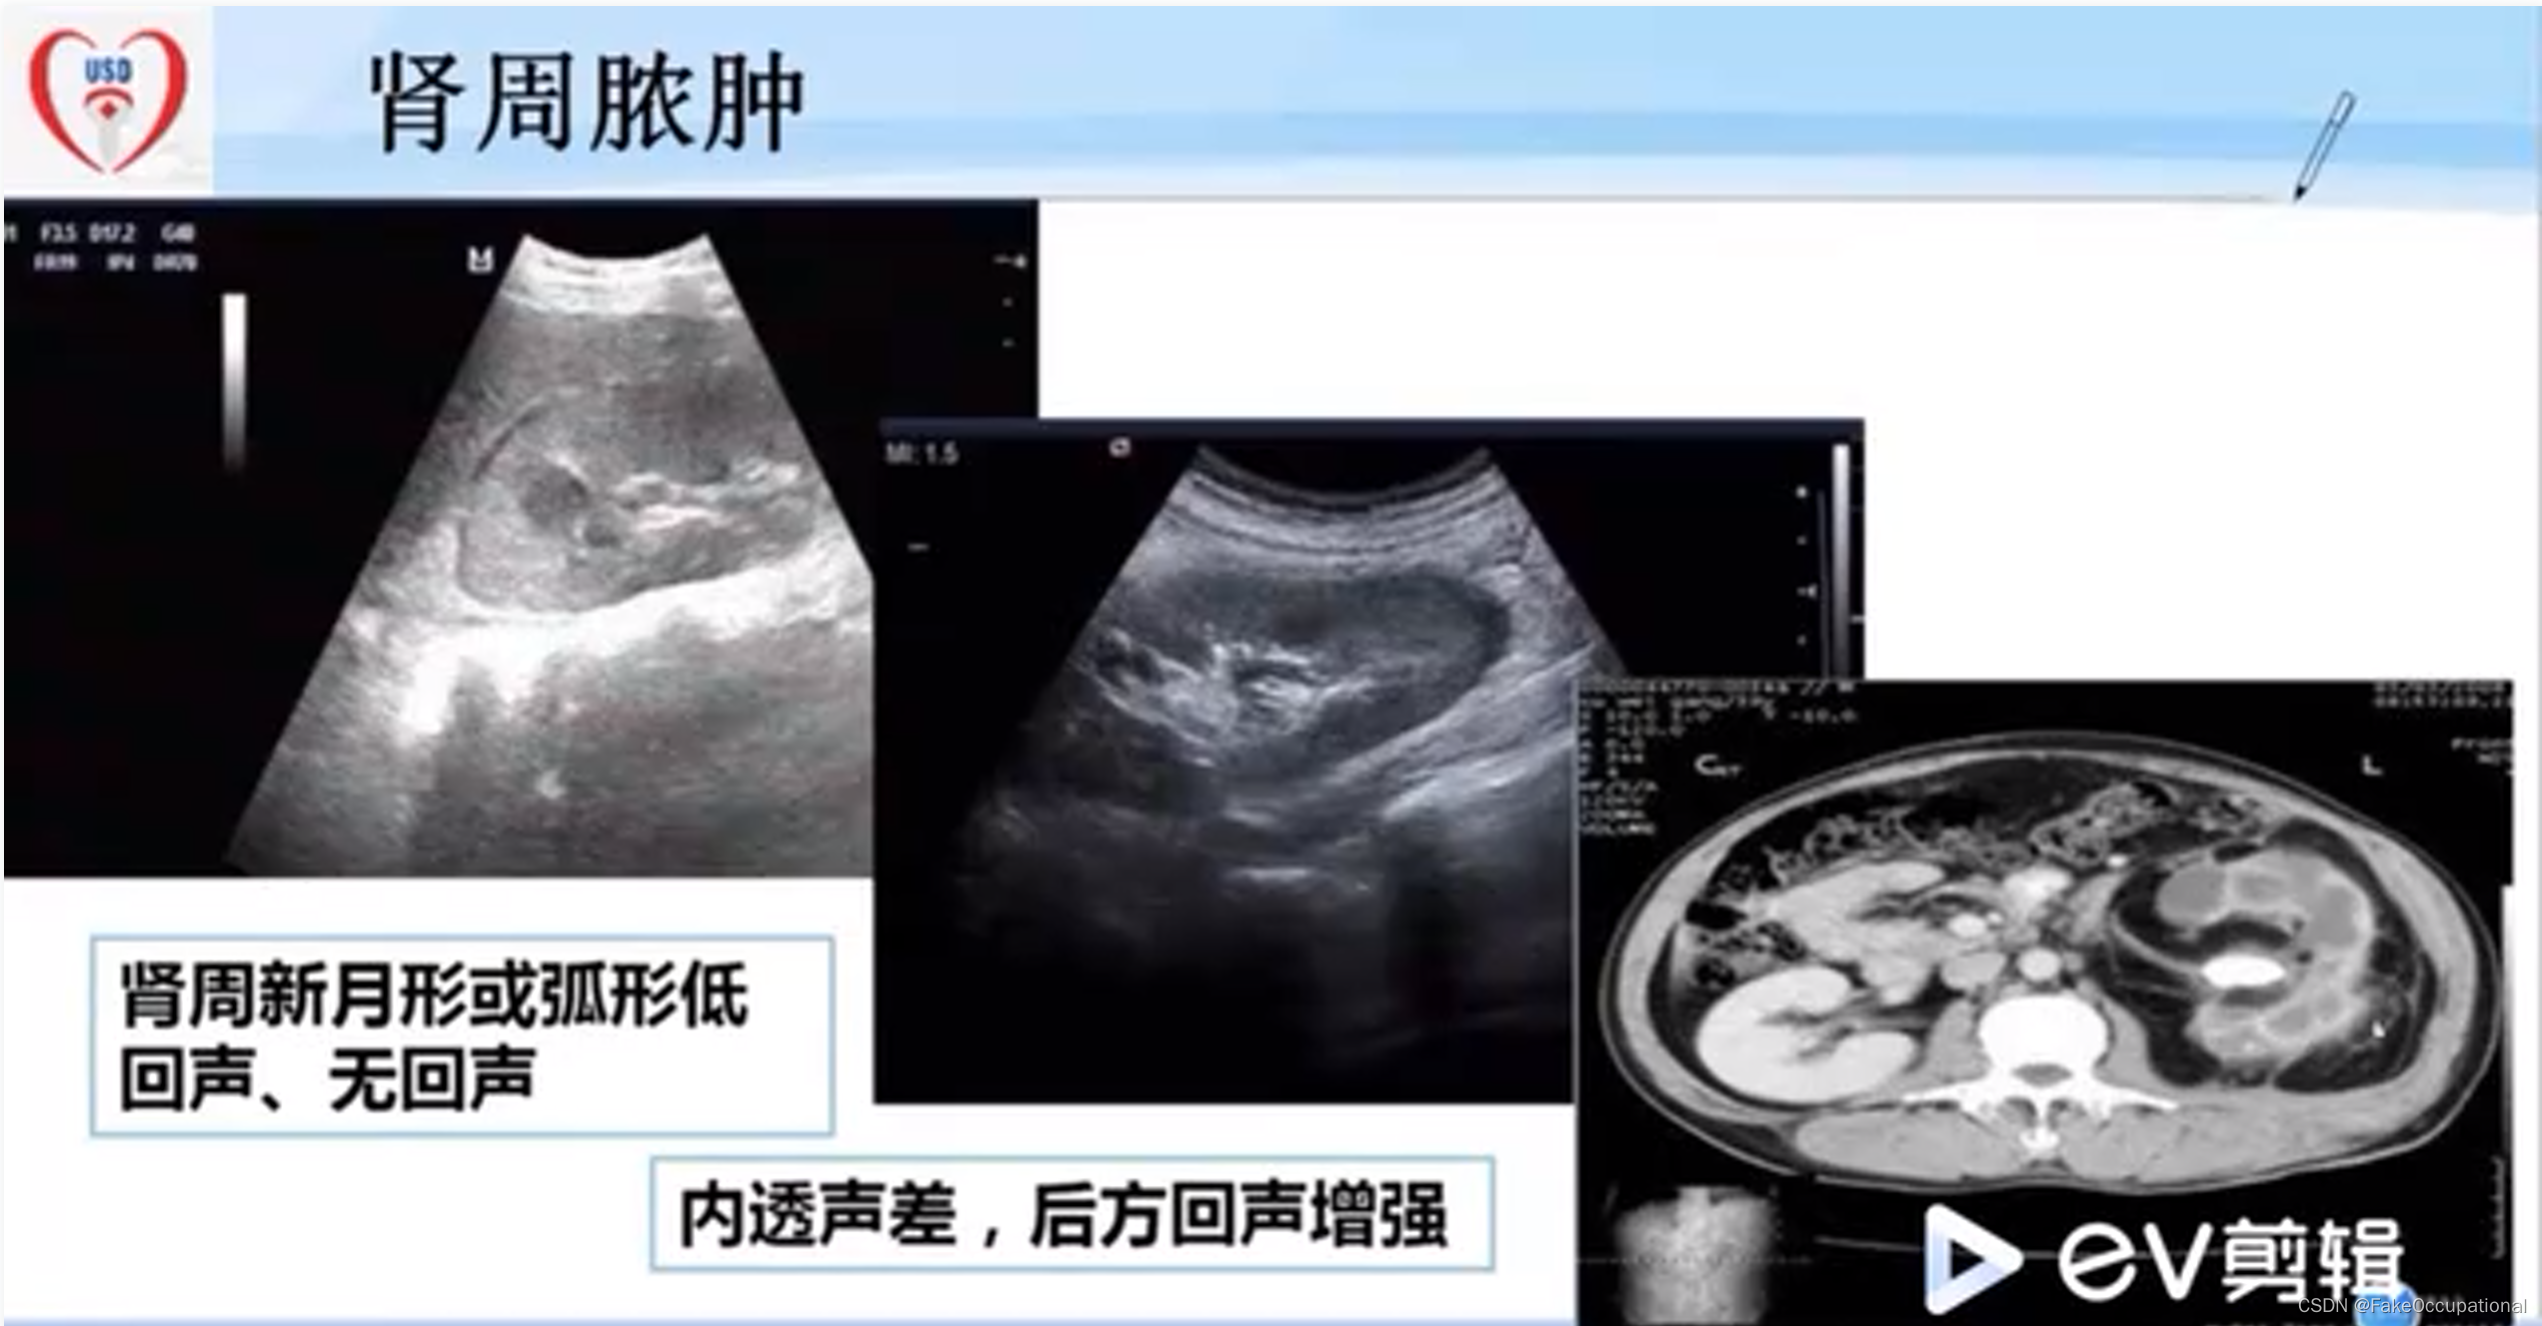

正常肾脏及肾血管超声表现

-

与正常肾脏造影相比,慢进快退

-

肾结核的超声显示的内部结构几乎完全消失

-

第三张图为CT结果